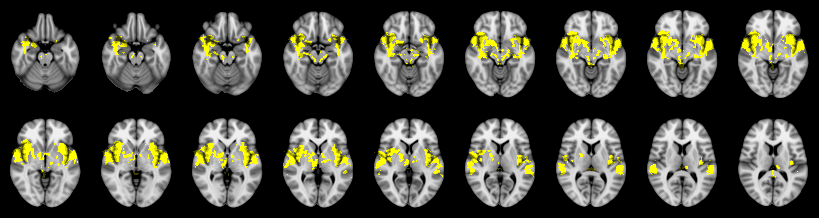

Combined

Hotelling T2: